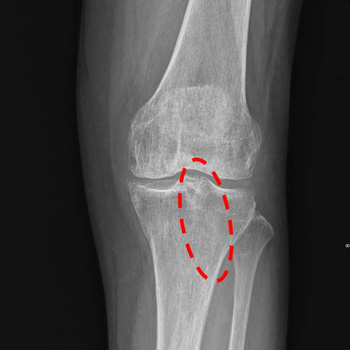

On October, 13 of 2024, I was on a pedestrian crossing and as the traffic light was changing to red, I hurried to run and missed my step. After slipping down, I ached severely in my left knee and had a difficulty walking properly. I narrowly came back home with the aid of those around me. In the morning of next day, I called my great parish pastor Geumran Hwang and she prayed for me over the phone. After that my pain was relieved and I went to the hospital for the examination. Through the X-ray result, the doctor said to me, “You have the left patella fracture, and need a surgery.” But I didn’t receive surgery and returned home wearing a cast. I thought over why this happened to me and looked back on my past days. And I repented of my hot-temper, ill-feelings, envy, judgment, condemnation, and of not praying fervently. Afterwards whenever I attended Sunday morning services, I received Senior Pastor Soojin Lee’s prayer for the sick. On October 29, Chinese Parishes 2 & 3 held a special prayer meeting for the fullness of the Spirit and I took a taxi with the help of my husband and my district leader to attend it. Speaker Pastor Miyoung Lee prayed for me and the fire of the Spirit came upon me. I felt like my head, waist, and legs became hot and refreshed. One the way back home after the meeting, there was no pain and I could step down on the ground with my left foot. I wanted to be healed completely and examined my life reading a religious book ‘The Message of the Cross.” I repented of my detailed wrongdoings such as not performing my missions sincerely. On November 1, I attended a Friday night service happily and then dreamed of Senior Pastor Soojin Lee. In my dream, she said to me, “Rise up and walk!” I woke up and became assured of my healing. Later I took off a cast and tried moving my leg. I was able to walk well without a cane I had leaned on. Hallelujah! In addition, I had felt a lump, the size of a cherry tomato, in the left neck from two years ago and in the morning one day I found it had also disappeared. I wanted to make it sure medically, and went to the hospital for the medical examination on November 14. The doctor said, “A patient with patella fracture cannot move their legs even after one month. It’s a miracle that you are able to move your leg just in three weeks even without surgery.” And he added, “Your fracture is completely restored, too!” Hallelujah! I give all my thanks and glory to Father God who healed me of patella fracture at the risk of surgery.

X-ray result

▲ After prayer: synostosis complete